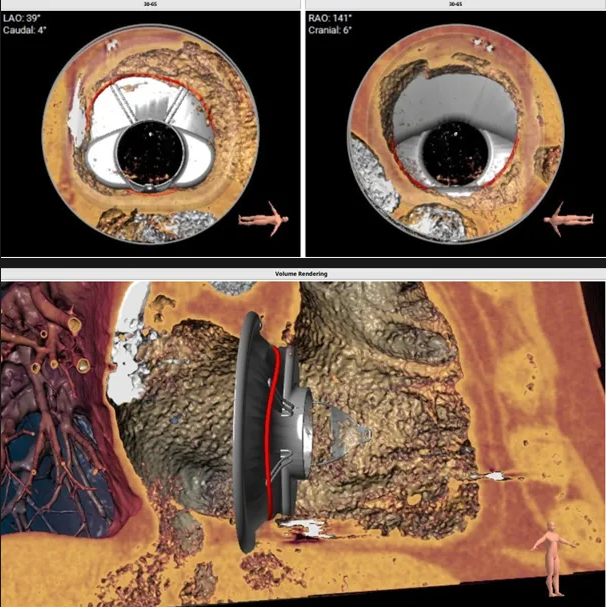

瓣膜植入模擬